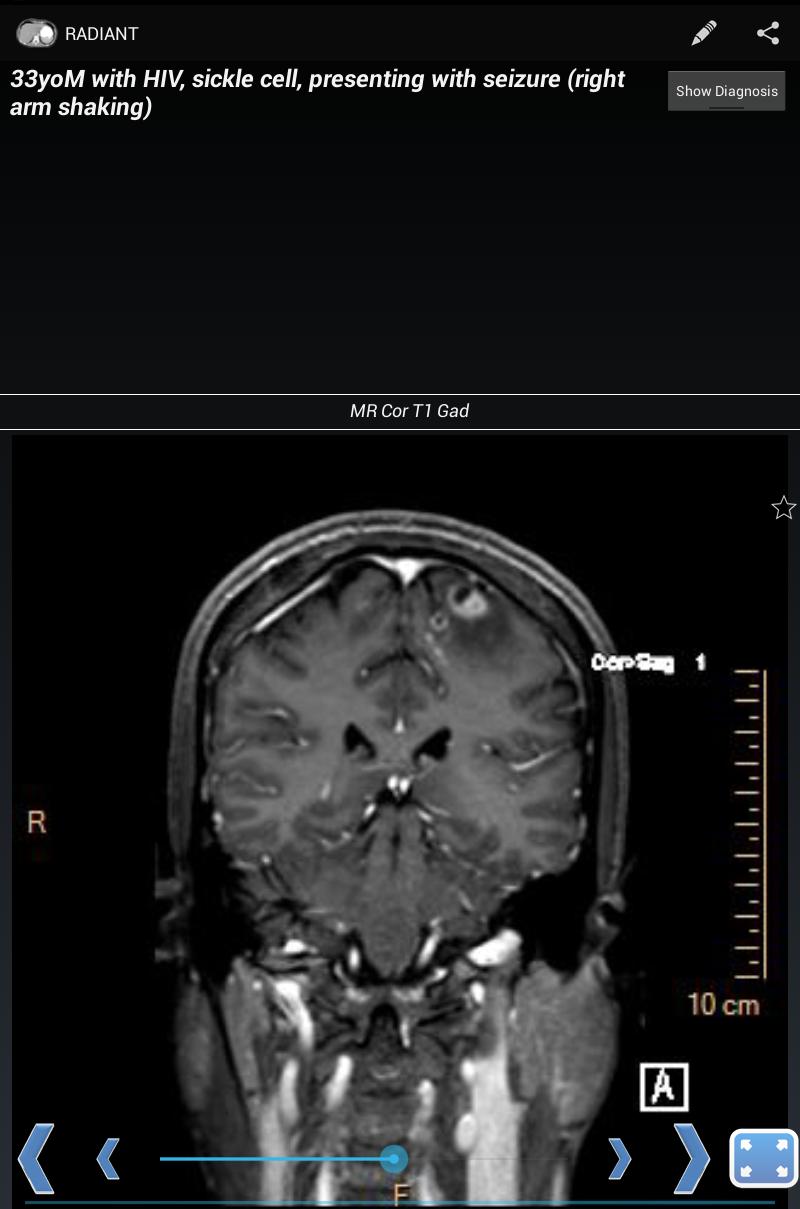

放射を使用すると、X線、超音波、CT、MRI、またはその他のイメージングモダリティを示すケースを作成できます。これは、実際の高品質の診断医療画像を使用して、胸部X線、正常な解剖学、および一般的な疾患プロセスを学ぶのに最適な方法です。